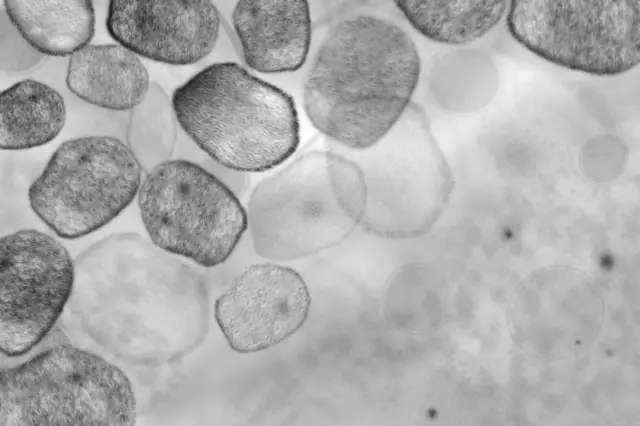

นี่คือการค้นพบล่าสุดของวงการบรรพจุลชีววิทยา (paleomicrobiology) ซึ่งนักวิทยาศาสตร์สกัดเอาชิ้นส่วนดีเอ็นเอของจุลชีพชนิดต่าง ๆ ไม่ว่าจะเป็นไวรัสหรือแบคทีเรีย จากร่างมัมมี่หรือโครงกระดูกของคนโบราณที่เก่าแก่หลายร้อยหรือหลายพันปี โดยชิ้นส่วนดีเอ็นเอเหล่านี้เมื่อถูกประกอบสร้างขึ้นใหม่ให้มีสภาพสมบูรณ์แล้ว จะสามารถบอกได้ว่าคนผู้นั้นเสียชีวิตด้วยสาเหตุใด และป่วยเป็นโรคอะไรบ้างเมื่อยังมีชีวิตอยู่